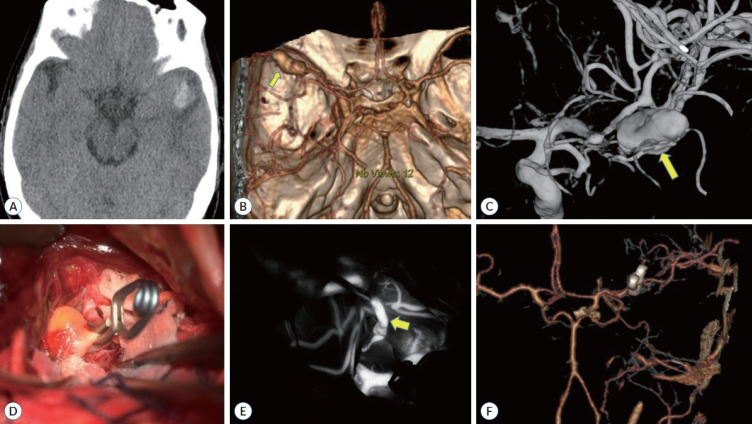

Abstract Image